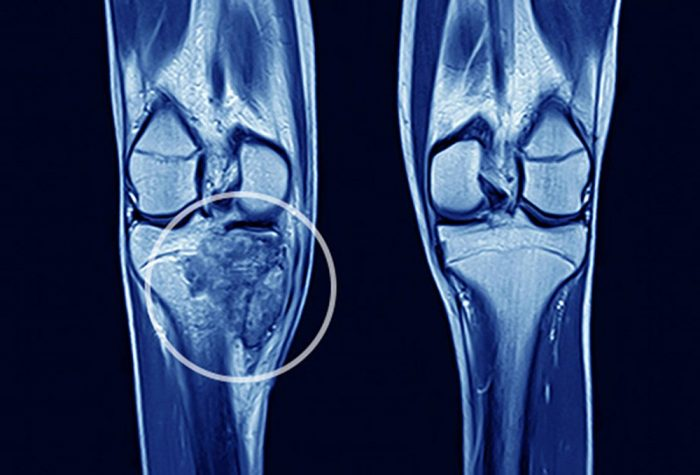

Tổng quan về ung thư di căn xương

Di căn xương thường xảy ra ở các vị trí như cột sống, xương chậu và đùi

Di căn thường bao gồm quá trình sau: Các tế bào ung thư xâm lấn mô bình thường gần đó, sau đó di chuyển qua thành bạch huyết hoặc mạch máu gần đó và bắt đầu lưu thông qua hệ thống bạch huyết và dòng máu để đến các bộ phận khác của cơ thể. Sau khi dừng lại ở các mạch máu nhỏ ở một vị trí xa hơn, chúng xâm lấn thành mạch máu và di chuyển vào các mô xung quanh, nơi chúng nhân lên và tạo thành các khối u nhỏ hơn. Những khối u mới này cần nguồn cung cấp máu để tiếp tục phát triển, vì vậy chúng kích thích sự phát triển của các mạch máu mới. Khi đã đến xương, các tế bào ung thư phải tránh các cuộc tấn công từ hệ thống miễn dịch của cơ thể. Điều này có nghĩa là khối u mới có thể hơi khác so với khối u nguyên phát. Điều này có thể làm cho nó khó khăn hơn để điều trị.